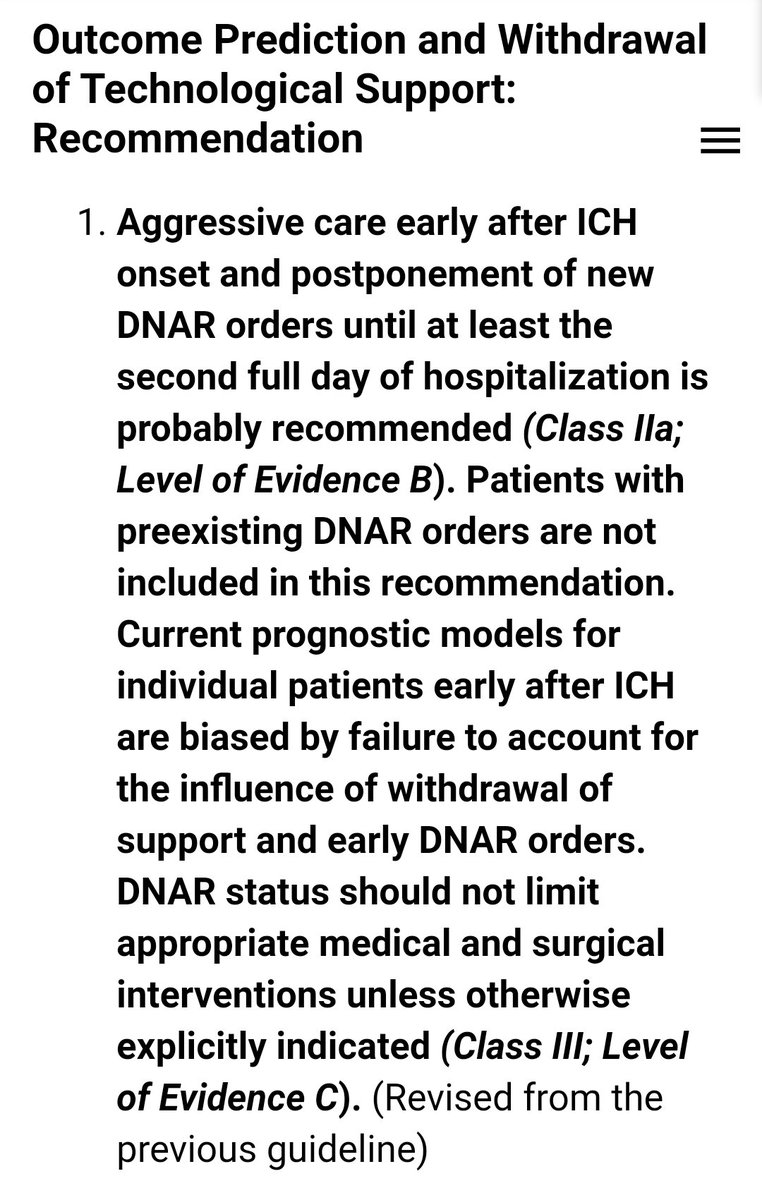

#السكته_الدماغيه_النزفيه

للاطباء🧠

Guidelines for the Management of Spontaneous Intracerebral Hemorrhage

👇👇full guidelines link 👇👇

ahajournals.org

للاطباء🧠

Guidelines for the Management of Spontaneous Intracerebral Hemorrhage

👇👇full guidelines link 👇👇

ahajournals.org